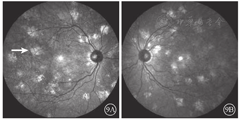

患者女,26岁,为例1患者女儿。因母亲诊断为Ⅰ型神经纤维瘤病于2018年1月16日到吉林大学第二医院眼科就诊。无异常视觉主诉,否认除母亲以外其他家人有相关症状体征。患者颜面及肢体见多个神经纤维瘤及咖啡斑(图6)。眼科检查:双眼视力1.0。双眼虹膜见Lisch结节(图7)。双眼眼前节大致正常。眼底彩色照相可见其黄斑区末梢血管略扭曲(图8)。红外眼底成像、EDI-OCT及ICGA检查表现与其母亲相似(图9,图10,图11)。诊断:Ⅰ型神经纤维瘤病。

在ICGA上,由于脉络膜结节对其上方脉络膜血流的影响,早期表现为与红外眼底成像强反射区域相对应的弱荧光区。随造影时间延长,弱荧光区域的面积逐渐减小乃至消失。有文献报道,绝大多数患者脉络膜结节对应的ICGA弱荧光会随着时间延长而逐渐减小,至30 min左右逐渐消失;仅有少数年龄较大,皮下神经纤维瘤更加严重的患者,直至造影晚期,仍然存在小片弱荧光[7]。本文例1患者,年长且皮下神经纤维瘤病变严重,ICGA 16 min中期像上存在弱荧光区域,甚至在30 min晚期像上仍然遗留小片弱荧光区域;病变较轻的例2患者,16 min中期像及30 min晚期像上弱荧光区域消失。